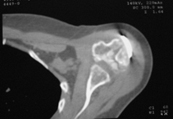

2.      Сохранение металлоконструкции с удалением выступающих за пределы головки винтов, релиз сустава, заполнение дефекта (b5_ct.jpg) на стыке метафиза и головки аутотрансплантатом для устранения «триггера», ранняя реабилитация.

Диагноз: неправильно сросшийся в условиях накостного остеосинтеза оскольчатый перелом головки левой плечевой кости (11-С3.2), асептический некроз головки плечевой кости, смешанная артро-миогенная контрактура левого плечевого сустава; демиелинизирующая нейропатия левого локтевого нерва.

Анализ ситуации позволяет считать, что основными причинами контрактуры являются неправильная репозиция фрагментов головки (разворот кверху и кзади), асептический некроз головки плечевой кости (отчетливое склерозирование на СТ).